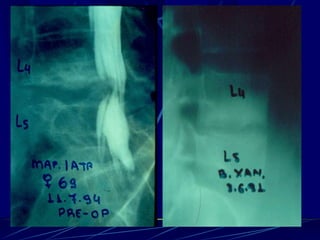

Φυματίωση της σπονδυλικής στήλης